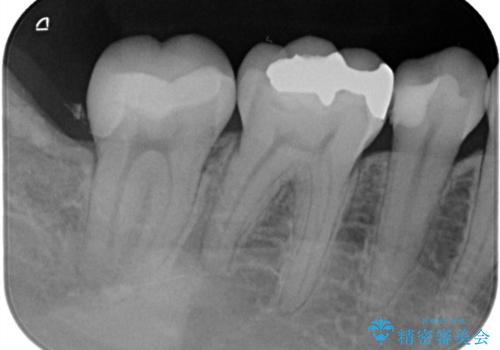

- 右下6番の奥歯に入っている金属の詰め物(メタルインレー)を気にされてご来院されました。お口の中の金属をなくしたいという患者様のご希望と、見た目の改善を目指し、天然歯に近い色と質感を持つセラミックインレーに交換する治療計画を立案しました。これにより、審美性の向上と、金属アレルギーのリスクがないメタルフリーの環境を実現することを目指しました。

治療では、まず古い金属のインレーを慎重に取り外し、内部に虫歯の再発がないかを丁寧に確認しました。歯を最小限だけ形成した後、精密な型取りから患者様の歯の色に合わせたオーダーメイドのセラミックインレーを作製しました。セラミックは、歯質との適合性が高く、プラークが付着しにくいため、虫歯の再発リスクを抑えるメリットもあります。適合性の高いセラミックインレーを装着することで、長年のコンプレックスだった銀歯がなくなり、機能的にも安定した自然な奥歯を取り戻していただけました。